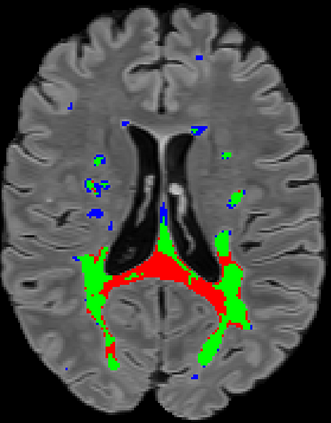

Recently, segmentation methods based on Convolutional Neural Networks (CNNs) showed promising performance in automatic Multiple Sclerosis (MS) lesions segmentation. These techniques have even outperformed human experts in controlled evaluation conditions such as Longitudinal MS Lesion Segmentation Challenge (ISBI Challenge). However state-of-the-art approaches trained to perform well on highly-controlled datasets fail to generalize on clinical data from unseen datasets. Instead of proposing another improvement of the segmentation accuracy, we propose a novel method robust to domain shift and performing well on unseen datasets, called DeepLesionBrain (DLB). This generalization property results from three main contributions. First, DLB is based on a large group of compact 3D CNNs. This spatially distributed strategy ensures a robust prediction despite the risk of generalization failure of some individual networks. Second, DLB includes a new image quality data augmentation to reduce dependency to training data specificity (e.g., acquisition protocol). Finally, to learn a more generalizable representation of MS lesions, we propose a hierarchical specialization learning (HSL). HSL is performed by pre-training a generic network over the whole brain, before using its weights as initialization to locally specialized networks. By this end, DLB learns both generic features extracted at global image level and specific features extracted at local image level. DLB generalization was validated in cross-dataset experiments on MSSEG'16, ISBI challenge, and in-house datasets. During experiments, DLB showed higher segmentation accuracy, better segmentation consistency and greater generalization performance compared to state-of-the-art methods. Therefore, DLB offers a robust framework well-suited for clinical practice.